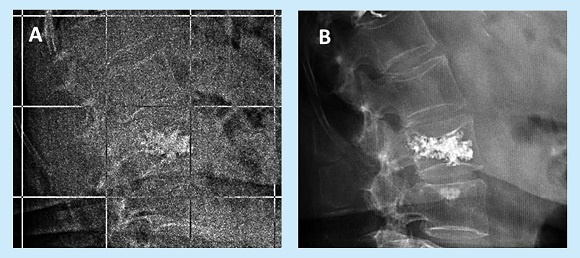

Además, en ningún caso se produjeron fracturas y/o pérdidas de altura en segmentos adyacentes a la fractura original (un único caso registró una nueva fractura no adyacente) ni tampoco se observaron fenómenos de osteólisis alrededor del PMMA inyectado o fragmentación del mismo en las imágenes analizadas correspondientes al PO=15a (Tabla 2, Figura 2).

En los 7 casos presentados, los pacientes mostraron estabilidad en los cuerpos vertebrales intervenidos a nivel de las paredes anterior, media y posterior habiendo transcurrido 15 ó más años desde la cirugía. Existen algunos datos publicados que asocian cambios en la angulación de los platillos tras una FV como factor de riesgo en cuanto a la aparición de nuevas FVs31,34. En nuestra serie de pacientes analizada no existieron diferencias clínicamente significativas en dicha angulación transcurridos 15 ó más años desde la cirugía, lo que podría justificar junto a otros factores como el mantenimiento de tratamiento osteoporótico que estos pacientes no hayan sufrido nuevas FVs en segmentos adyacentes.

A diferencia del PMMA de las PTCs, en la VP el cemento se halla interdigitado en el hueso trabecular, sin exponerse a fuerzas directas de compresión. Ésta puede ser la causa por la que, tal y como presentamos en nuestra serie de casos, no se observe fragmentación de PMMA ni fenómenos de osteólisis en el PO=15a.